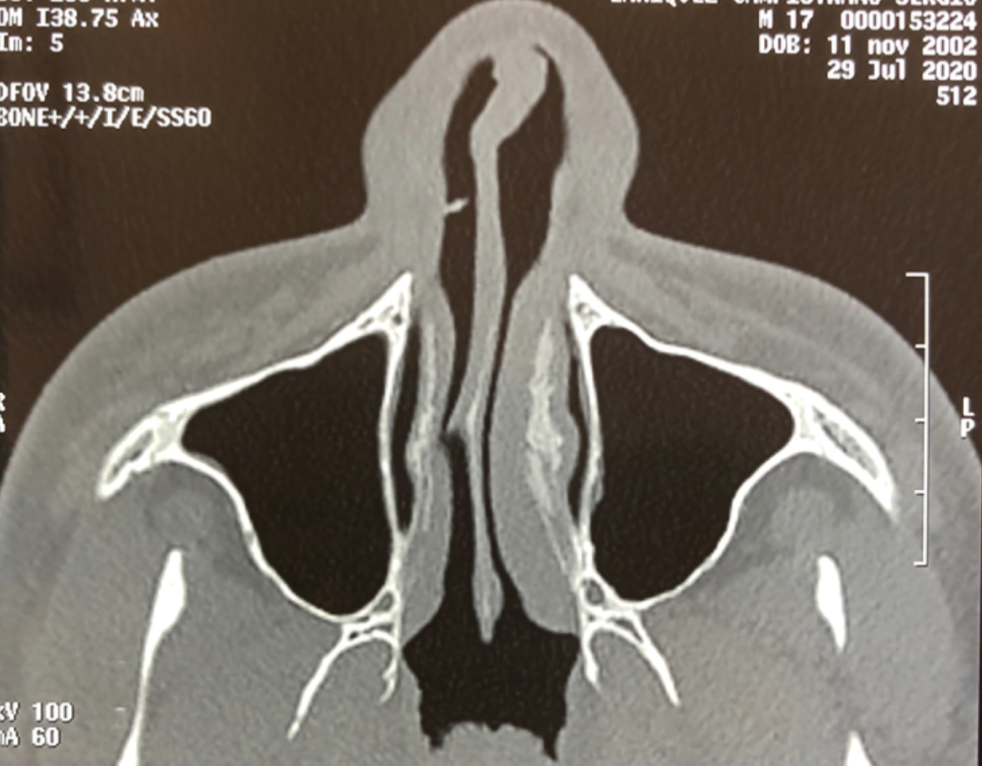

Q

Diagnóstico de imagen:

A

• Fractura del septum cartilaginoso y una desviación congénita